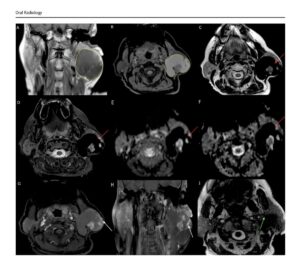

Образните изследвания – компютърна томография и мултипараметрична магнитнорезонансна томография – разкриват характерни особености на тумора. На MRI се установява специфична комбинация от находки: силно понижен сигнал на определени последователности („signal void“), повишен сигнал на T1-претеглени изображения и минимално контрастно усилване на кистозните части на лезията, като усилване се наблюдава основно в папиларните структури. При двата случая е установено изместване,

но не и инфилтрация на лицевия нерв – ключова информация за безопасното хирургично лечение.